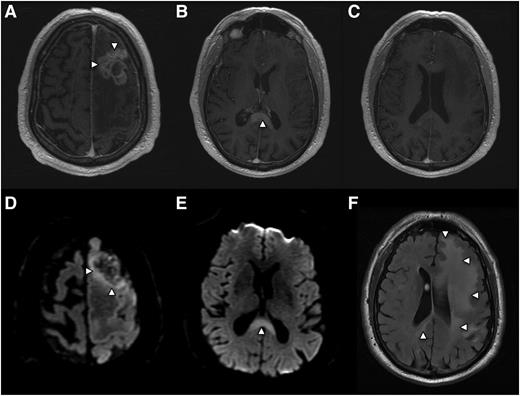

While approximately 50% of PCNSL tumors in immunocompetent patients present as a solitary enhancing brain lesion on T1-weighted MRI, ∼25% of tumors at baseline are associated with a separate, nonenhancing lesion that is hyperintense on T2/FLAIR (fluid attenuated inversion recovery)-weighted imaging at a locus that is distinct from the enhancing lesion(s).9 This observation is consistent with the fact that lymphomatous dissemination in the brain may occur in the absence of contrast enhancement on MRI (Figure 2).

Radiographic presentation of multifocal PCNSL, characterized by distinct MRI sequences. (A) T1 postgadolinium image demonstrates an enhancing mass involving the left frontal lobe (arrows) with central necrosis and surrounding vasogenic edema. On spectroscopy the mass demonstrated increased tumor metabolites, lactate, and choline (not shown). (B) An apparently isolated, second homogeneously enhancing mass (arrow) is identified inferiorly, involving splenium of the corpus callosum. (C) No enhancing foci are detected in white matter between the 2 distinct lesions. (D) Diffusion-weighted imaging demonstrates foci of reduced or restricted diffusion (arrows), suggestive of dense cellularity, in the superior aspect of the frontal mass. (E) Restricted diffusion within the enhancing lesion involving the corpus callosum, strongly suggestive of lymphoma. (F) Extensive T2/FLAIR signal hyperintensity (arrows) extending from the frontal mass posteriorly to the corpus callosal lesion, consistent with nonenhancing lymphoma dissemination involving the cerebral hemisphere.

While T2/FLAIR images may detect subclinical, nonenhancing dissemination of CNS lymphoma, confounding MRI abnormalities involving white matter are commonly elicited by the effects of chemotherapy, including HD-MTX, brain irradiation, and normal aging. For this reason there is interest in development of novel, advanced imaging approaches to noninvasively detect and provide prognostic insight into PCNSL. One approach is diffusion-weighted imaging, which measures restricted water diffusion in hypercellular tumors such as PCNSL, resulting in hyperintensity on MRI that can distinguish CNS lymphomas from less cellular tumors such as malignant gliomas. Foci of restricted diffusion may be useful to discriminate residual CNS lymphoma from benign processes, and very low diffusion coefficients have been associated with high-risk, aggressive CNS lymphoma (Figure 2).10 Other advanced imaging approaches include magnetic resonance spectroscopy and positron emission tomography (PET), each of which are capable of detecting tumor-associated Warburg metabolism.11